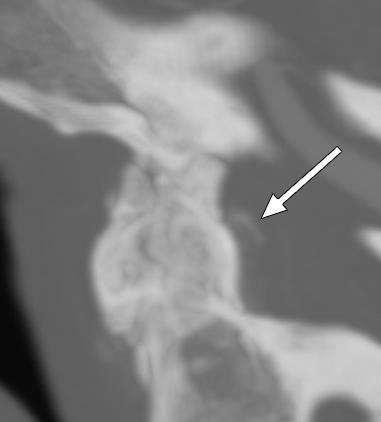

381 A Diagnosis Fit for a Queen: Crowned Dens Syndrome

EN Dankert Eggum, SA Schroeder Hevesi, B Sandefur